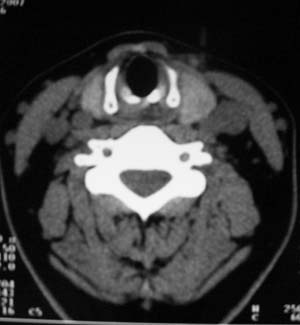

以下是引用zsl6918在2007-8-27 14:40:00的发言:[br]双侧甲状腺多发性低密度占位,边界清晰,密度欠均匀,尤以左侧明显,与周围组织分解清,考虑多发性腺瘤可能性大,不除外结节性甲状腺肿

以下是引用liaizhi在2007-8-27 15:20:00的发言:[br]双侧甲状腺散在多个囊性第密度影,左侧最大一个病灶与正常甲状腺分界尚可,气管受压稍右移。考虑甲状腺瘤的可能性大。

以下是引用zsl6918在2007-8-27 14:40:00的发言:[br]双侧甲状腺多发性低密度占位,边界清晰,密度欠均匀,尤以左侧明显,与周围组织分解清,考虑多发性腺瘤可能性大